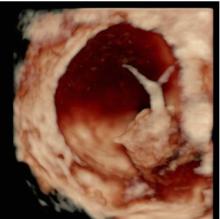

L’expertise dell’operatore, associato all’acquisizione da parte dell’Istituto di un’apparecchiatura di alto livello, dotata di software di ultima generazione anche con 3D e 4D, permettono di caratterizzare nei minimi dettagli l’eventuale presenza di patologia ovarica e di verificare l’eventuale disseminazione limitrofa agli organi circostanti. Questo da una parte dovrebbe permettere di evitare di misconoscere o sottovalutare alcune patologie ovariche potenzialmente evolutive in senso maligno e pertanto da indirizzare a trattamento chirurgico, e dall'altra di condurre un follow-up ecografico ad alcune patologie ovariche definite benigne secondo criteri standardizzati e ampiamente validati atti ad evitare una chirurgia non necessaria. Nel gruppo di lavoro IOTA infatti si è visto in questi anni che quasi l'80 percento delle masse ovariche operate risultavano benigne. E’noto che ogni procedura chirurgica è associata a possibili complicanze a breve come a lungo termine.